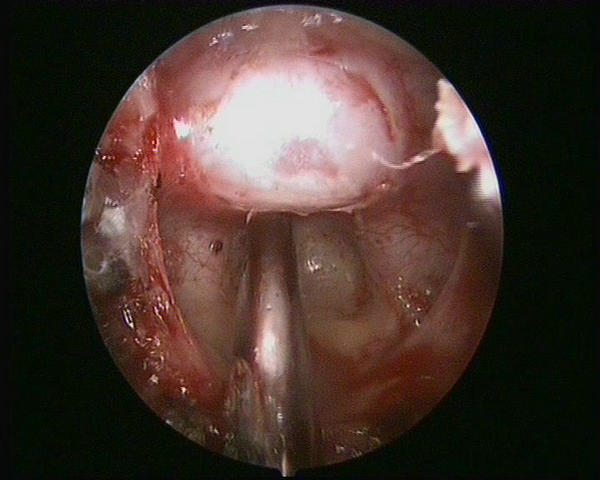

近两个多月来,患者王女士感到右眼视力明显下降,伴有头痛,起初她以为是近视加深,没想到到郑州大学五附院检查,头部磁共振在她的脑袋里找到一颗红枣大小的脑垂体瘤(图1)。

图1